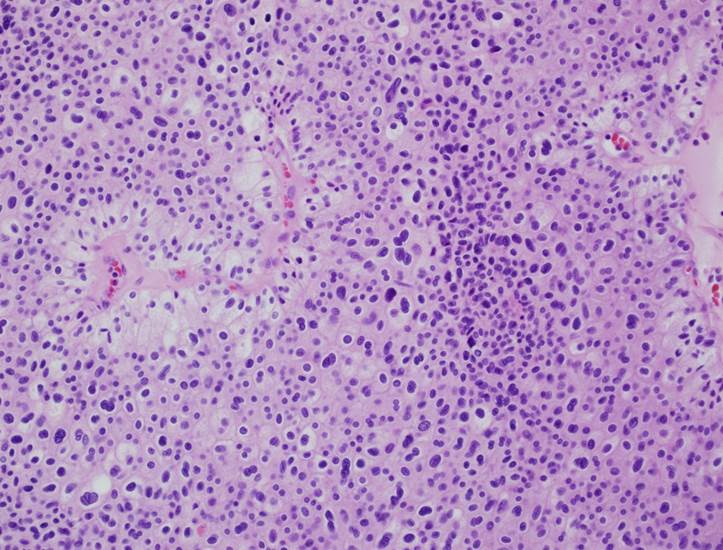

Consensus grade: I would not grade this tumor

Chromophobe |

chromophobe RCC? grading? |

Case description (by case creator):